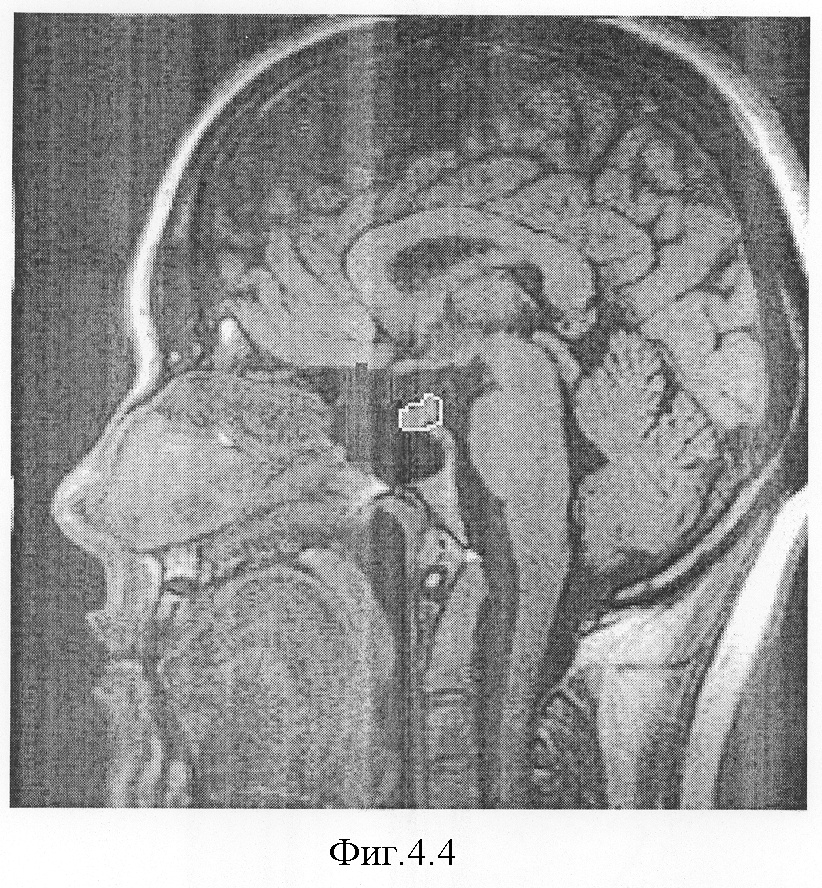

На фиг.4.1-7 показаны результирующие семь изображений, проходящие в сагиттальной плоскости через гипофиз. При этом фиг.4.1 проходит в непосредственной близости от турецкого седла справа, через сифон внутренней сонной артерии, гипофиз не затрагивает;

фиг.4.4 – область гипофиза с приподнятой задней долькой, обведена пунктиром, его площадь в сагиттальном сечении равна 0,5 см2;